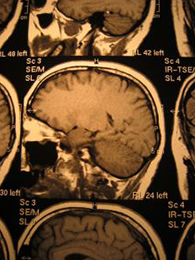

翌日になると妻は言葉数が極端に少なく、全身に力が入らないようでした。私は心配になって、近くの総合病院に電話をかけて症状を相談しました。すると、電話がドクターに回され、私の話を聞いたドクターは「いまからすぐに奥さんを連れてきてください」と言ってくれました。そこで、またタクシーを呼んで妻を病院に連れて行ったところ、すぐに脳のCT検査となり、脳梗塞を起こしていると診断されたのです。

その後の精密検査で、心臓の中の血栓が脳に飛んだタイプの脳梗塞ではなく、脳の動脈硬化で血管のなかが詰まったことによって起こった脳梗塞と言われました。